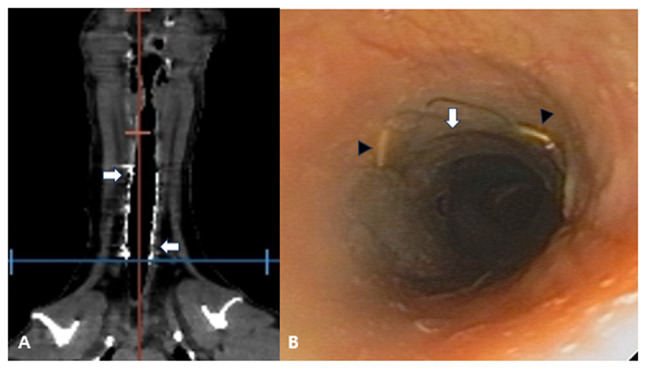

Materials and methods: A double-wire woven nitinol stent was handmade using a cross-and-hook knitting method. The fabricated endotracheal stent was 2-3 mm larger than the internal diameter of the ruptured trachea. The clinical signs and respiratory pattern, image diagnoses (radiography and computed tomography), and tracheoscopy results after endotracheal stenting were assessed for six months.

Results: The lateral cervical radiographs showed that the intratracheal stent was properly placed without migration or stent fracture at the insertion site. After two to three weeks of tracheal stenting, the coughing and dyspnea signs revolved, and the normal activities in all dogs were resumed.